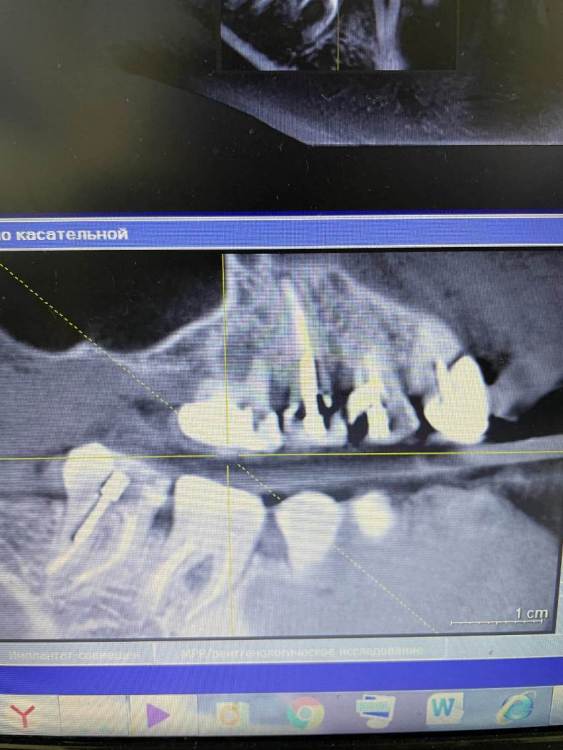

Irouil Опубликовано 21 октября, 2021 Поделиться Опубликовано 21 октября, 2021 Чтобы оценить прогноз перелеченных зубов надо увидеть ещё и снимки до лечения чтобы сравнить что было с тем, что стало. Такой вид снимка очень малоинформативен, я рекомендую либо выложить срезы из КТ интересующих Вас областей, либо выложить всю КТ 1 1 Ссылка на комментарий

Amparo743 Опубликовано 21 октября, 2021 Автор Поделиться Опубликовано 21 октября, 2021 @Irouil благодарю вас за ответ. К сожалению не знаю как извлечь из этой программы срезы или всю Кт. Мне отдали снимок на диске. И на этот снимок показывал врач и видел во всех этих зубах патологию, показывая именно с панорамы. Ссылка на комментарий

Irouil Опубликовано 21 октября, 2021 Поделиться Опубликовано 21 октября, 2021 Можете попробовать скинуть КТ в терапевтической ветке, тут надо его хорошенько посмотреть у каждого зуба чтобы оценить шансы на перелечивание, да и снимки до лечения было бы неплохо увидеть - может там динамика к улучшению стремится, но пока, судя по тем срезам что я вижу, вероятнее всего зубы действительно нужно будет удалять. Ссылка на комментарий

Bier Опубликовано 21 октября, 2021 Поделиться Опубликовано 21 октября, 2021 воспаление есть, скорее всего хирург прав, еще одно перелечивание они не перенесут. Ссылка на комментарий